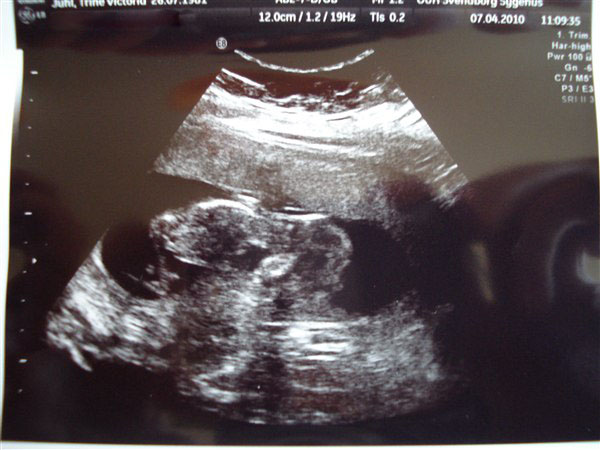

okay! så jeg lagde mig på briksen og fik trukket temmelig godt ned i bukserne og en ordentlig klat "smør" på maven og DER lå vores baby

babyen spjættede og rullede og tørrede sig i øjnene på præcis samme måde som August (vores kat) og slog ud med armene og hoppede med numsen - det ER en rumpenisse, der var godt gang i bagen på den

og lige på det første billede kunne vi allesammen med det blotte øje se, at nakkefolden var meget meget tynd. men så blev lægen så ivrig efter at vise os hvor fin den var, at han glemte at tage billede, så han måtte scanne og scanne og scanne og jeg måtte flere gange løfte bækkenet og vrikke med måsen og til sidst kom sygeplejersken og forsøgte og så fik de den endelig målt. da de så havde tastet alt ind i systemet udbrød de begge to "ja, det er meget, meget lavt!" og smilede over hele femøren. "din termin bliver rykket til 13. oktober (på Carlas fødselsdag) og din baby har det rigtig godt, tallet er 1:15000, det er en meget meget meget lille risiko"

I får lige et par snapshots, den ligger ligesom på maven med hovedet ude til venstre: